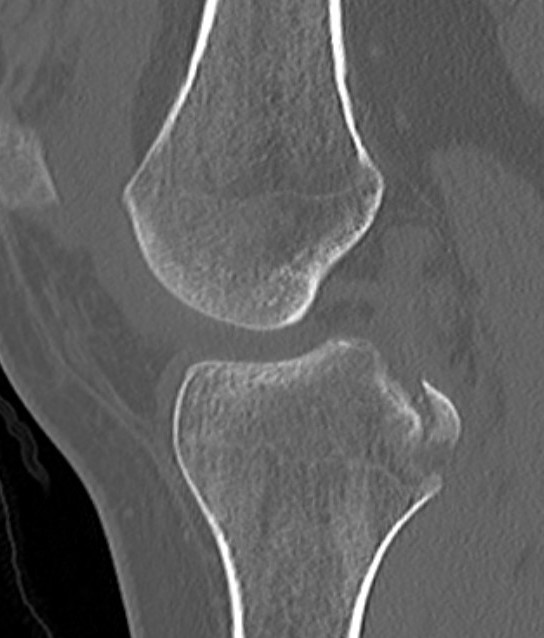

Bony Avulsion

Chronic bony avulsion PCL

Posterior subluxation of tibia

Grade 3 PCL disruption - posterior tibia subluxed behind posterior aspect femoral condyles